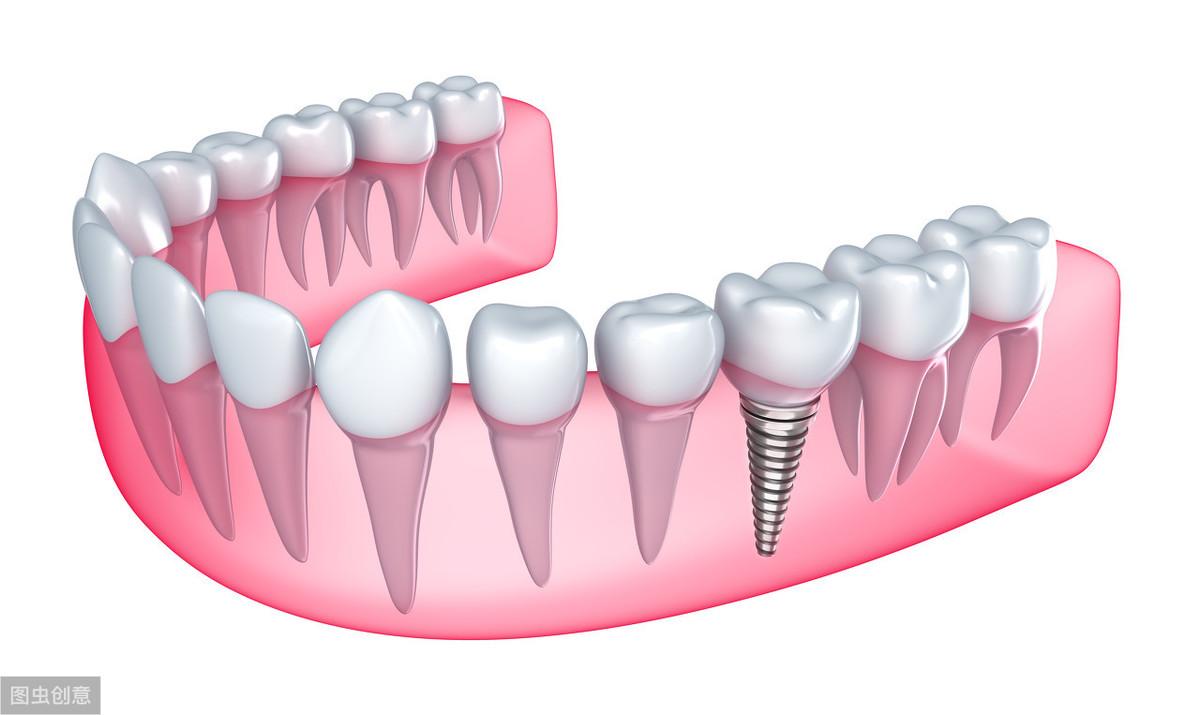

種植牙技術(shù)是近幾十年出現(xiàn)在大眾視野中的一種修復(fù)缺失牙體的方法。一顆完整的種植牙體由三部分組成:種植體、基臺、人工牙冠。

手術(shù)過程就是將種植體植入患者的牙體缺失處,待其傷口愈合,種植體與牙槽骨結(jié)合牢固后,將基臺安裝在種植體上,再將人工牙冠安裝在基臺上,形成完整而堅固的人工牙體。

種植牙技術(shù)就像在缺失牙體處種一顆新的牙齒,能夠和牙槽骨結(jié)合,做種植牙能有預(yù)防牙槽骨萎縮,這是普通的假牙無法做到的,而且種植牙體不依附周圍鄰牙,對鄰牙不造成任何負擔(dān),所以相對其他修復(fù)手段,不僅更為牢固不易松動,且使用壽命長,果好。